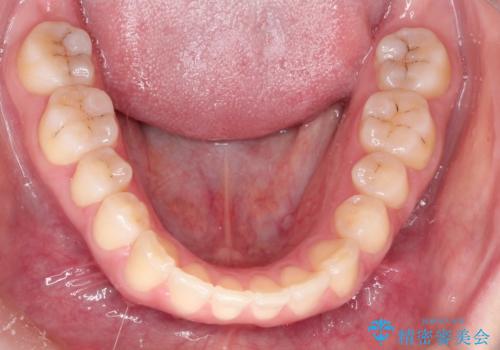

上下の前歯が当たらない インビザラインによる開咬の矯正治療

開咬とよばれる、奥歯しか上下の歯が接触していない状態でした。

舌の使い方が上手ではなかったので、治療と同時に舌のトレーニングを行いました。

舌の使い方も矯正治療と非常に関係があります。